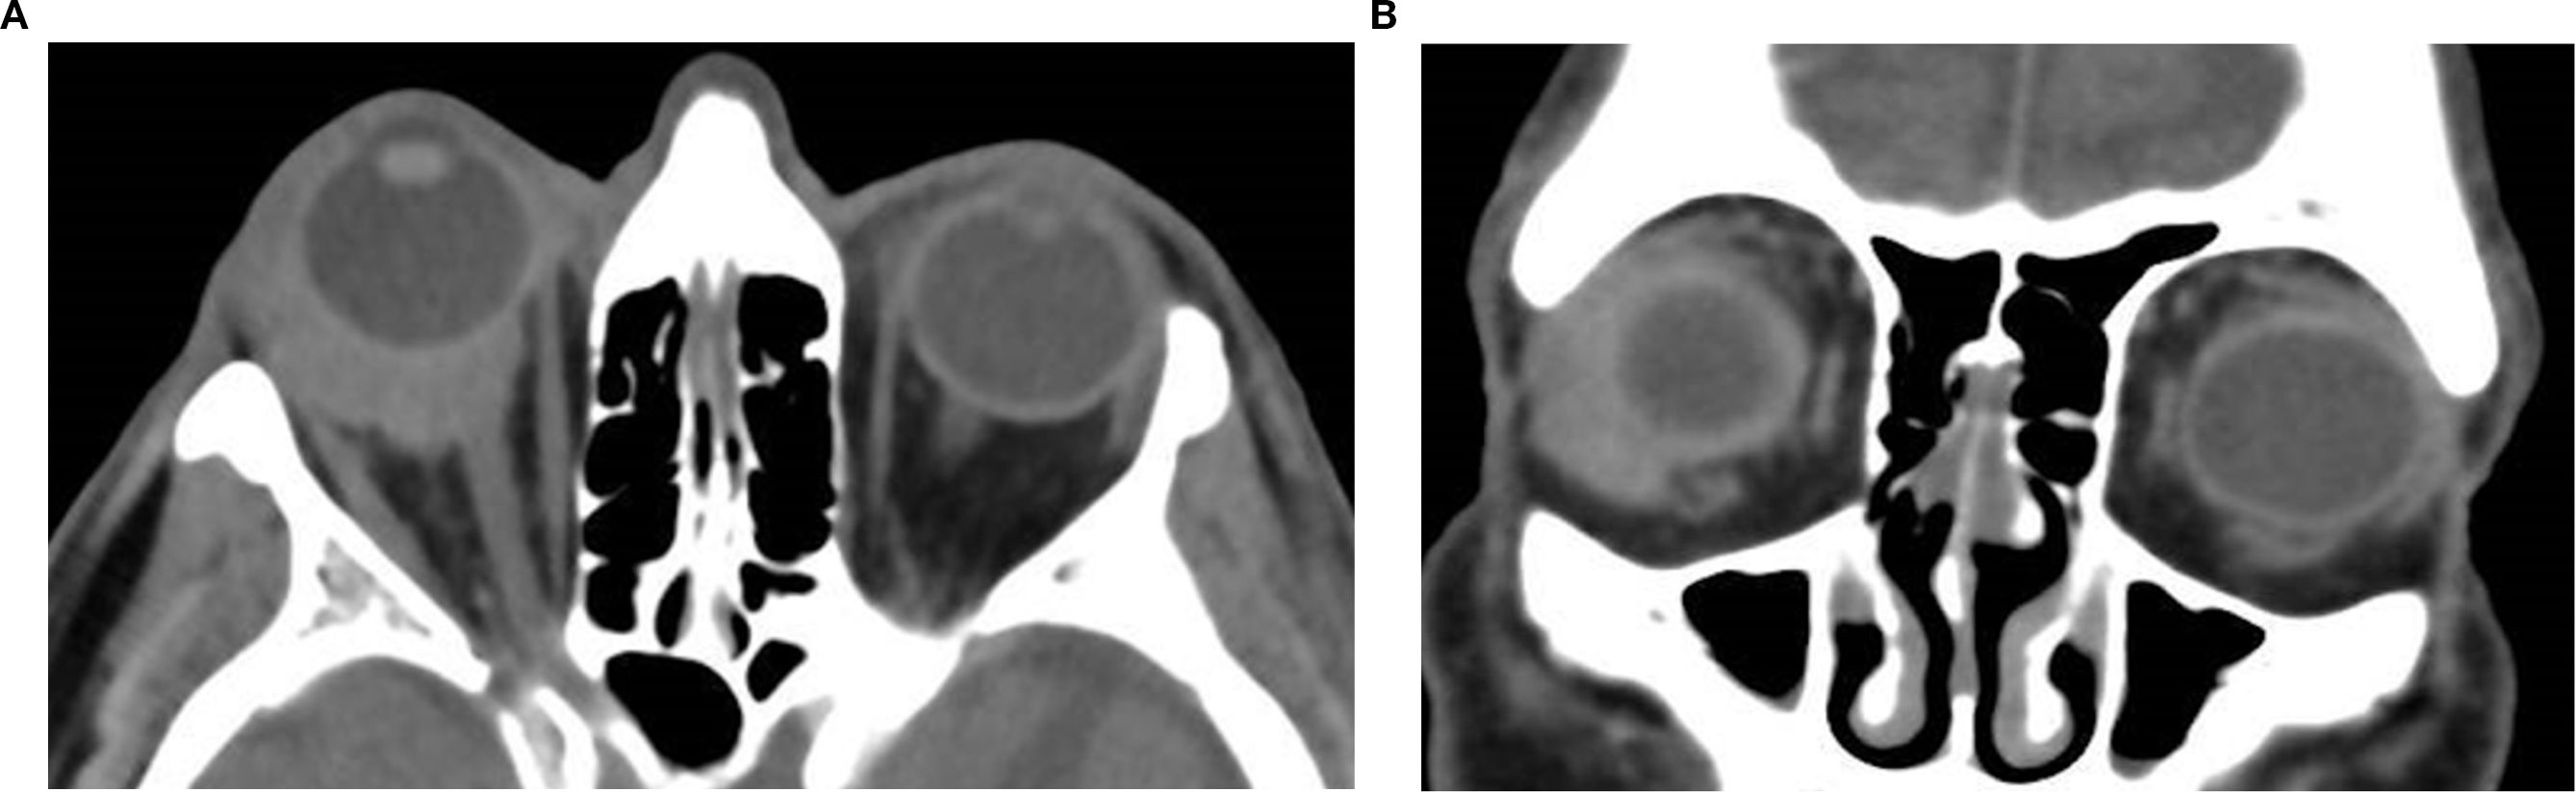

Orbital masses include a diverse spectrum of benign, malignant, inflammatory, and vascular lesions in pediatric and adult patients. Accurately diagnosing the type of lesion is critical, as management strategies differ significantly. Advanced imaging is therefore essential, and computed tomography (CT) is central to orbital evaluation. We reviewed the literature to synthesize evidence on CT features across common orbital pathologies and correlated imaging with clinical presentation to emphasize diagnostic relevance. CT characteristics are summarized for vascular lesions (cavernous venous malformation, lymphatic malformation), inflammatory conditions (orbital myositis, dacryoadenitis), benign lesions (dermoid cyst, pleomorphic adenoma), and malignant lesions (lacrimal gland lymphoma, adenoid cystic carcinoma, rhabdomyosarcoma). We present characteristic patterns of location, morphology, enhancement, and bone change, with practical discriminators and common pitfalls to aid differentiation. When used alongside clinical context, CT remains a preferred modality in many clinical settings due to its rapid acquisition, wide availability, and reliable depiction of bone and calcifications. It supports accurate diagnosis and informed management decisions in time-critical settings. This review provides a structured reference for interpreting CT findings across a wide range of orbital disease.